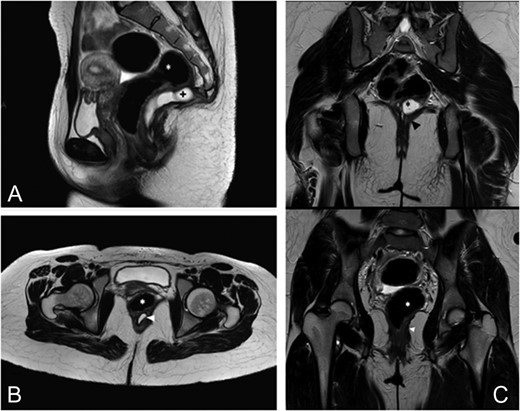

At 8 months follow-up the patient complaint of mild constipation. On digital rectal examination a small (2–3 cm) tender fluctuant extraluminal retrorectal mass was palpable above the anal verge. At MRI the TSE T2-weighted image shows a recurrent cystic lesion expanded in the posterior pararectal space in the context of the levator ani muscle (Fig. 2A–C).

Eight months follow-up MRI. (A) This sagittal TSE T2-weighted image shows a recurrent cystic lesion (+) expanded in the posterior pararectal space, containing serum-proteinaceous material, following the course of the rectal distal portion (*) in the context of the levator ani muscle. (B) Axial TSE T2-weighted images show the cystic lesion (arrowhead) closely adhering to the posterior rectal wall. (C) Coronal TSE T2-weighted images demostrate the relations among the cystic lesion (black*), the rectum (white*) and the levator ani muscle (arrowhead).

The MRI findings at 8 months follow-up have mimicked recurrent cyst, not confirmed by the pathology report. Normally, surgical excision of gastrointestinal duplication cysts is generally curative; however, follow-up is important after the treatment.